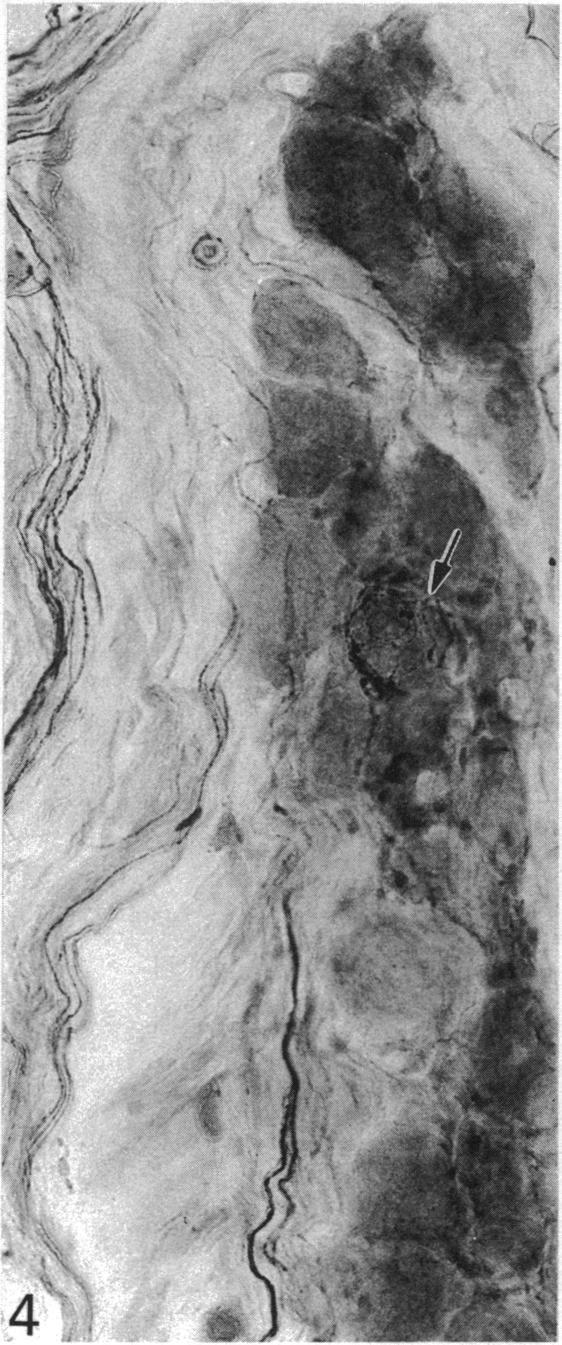

The quantitative cell count showed the presence of about 20,000 ganglion cells with associated satellite elements in the nodose ganglion in the monkey. Among these closely packed cells, at least one-third were substance P (SP) immunoreactive, ranging from faint or moderate to intense staining. Substance P immunoreactivity (SP-IR) was localised in the cell bodies and their long extending neurites. Ultrastructural study showed that SP-IR was not associated with any particular organelles or inclusions. A striking feature of the nodose ganglion was the occurrence of SP-positive pericellular arborisations associated with about 0.5% of the ganglion cells which were almost exclusively SP-negative. The pericellular arborisation displayed diverse morphological forms from a simple tortuous fibre to complex glomerular networks or plexuses encircling the soma of SP-negative ganglion cells. The varicose nerve fibres forming the pericellular arborisations appeared to terminate as 'boutons' contacting the soma of the ganglion cells. Electron microscopic study demonstrated the close spatial relation between the SP-IR profiles and the ganglion cell but there was no direct synaptic contact. In some instances, the SP-IR profiles containing agranular and dense-cored vesicles penetrated the cytoplasm of satellite cells, almost reaching the surface of the soma of the ganglion cell. The sources of origin of the nerve plexuses in the pericellular arborisation were either from the small and sparsely distributed jugular ganglion cells which were intensely SP-IR or from the intrinsic SP-IR nodose ganglion cells. The possibility that the efferent neurons in the dorsal motor nucleus of the vagus could also contribute to the pericellular arborisation was also considered. The function of the pericellular arborisations may be related to the modulation of the SP-deficient ganglion cells with which they associate through the release of SP and probably by way of the satellite cells.

定量细胞计数显示,猴子的结状神经节中存在约20,000个神经节细胞及相关的卫星细胞。在这些紧密排列的细胞中,至少三分之一对P物质(SP)呈免疫反应性,染色强度从微弱、中等至强烈不等。P物质免疫反应性(SP-IR)定位于细胞体及其长延伸的神经突。超微结构研究表明,SP-IR与任何特定的细胞器或内含物无关。结状神经节的一个显著特征是,约0.5%的神经节细胞周围出现SP阳性的树枝状分支,而这些神经节细胞几乎完全为SP阴性。细胞周围的树枝状分支呈现出多种形态,从简单的曲折纤维到复杂的肾小球样网络或围绕SP阴性神经节细胞胞体的丛状结构。形成细胞周围树枝状分支的曲张神经纤维似乎以“终扣”的形式终止于与神经节细胞胞体接触处。电子显微镜研究显示,SP-IR结构与神经节细胞之间存在紧密的空间关系,但没有直接的突触联系。在某些情况下,含有无颗粒和致密核心小泡的SP-IR结构穿透卫星细胞的细胞质,几乎到达神经节细胞胞体表面。细胞周围树枝状分支中的神经丛来源要么是来自强烈SP-IR的小而稀疏分布的颈静脉神经节细胞,要么是来自结状神经节内源性的SP-IR细胞。迷走神经背运动核中的传出神经元也可能参与细胞周围树枝状分支形成的可能性也被考虑在内。细胞周围树枝状分支的功能可能与其通过释放SP并可能通过卫星细胞对与之相关的SP缺乏神经节细胞的调节有关。